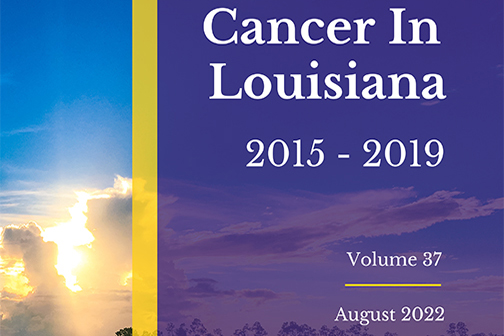

LSU Health’s LA Tumor Registry Publishes Latest Statewide Cancer Incidence, Mortality & Survival Info

LSU Health New Orleans’ Louisiana Tumor Registry has published the latest volume in its annual Cancer in Louisiana monograph series. Cancer in Louisiana, Volume 37, 2015 – 2019, documents cancer incidence and mortality from 2015 to 2019 in Louisiana, as well as incidence and mortality trends from 1988 to 2019. It also includes survival statistics for cases diagnosed from 2008 to 2018 and followed into 2019, as well as prevalence for cancer cases diagnosed from January 1, 2000, to January 1, 2019. More